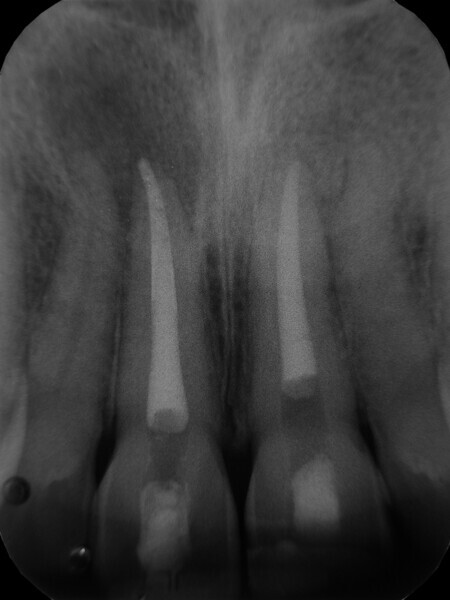

Irrigating the root canal: A case report